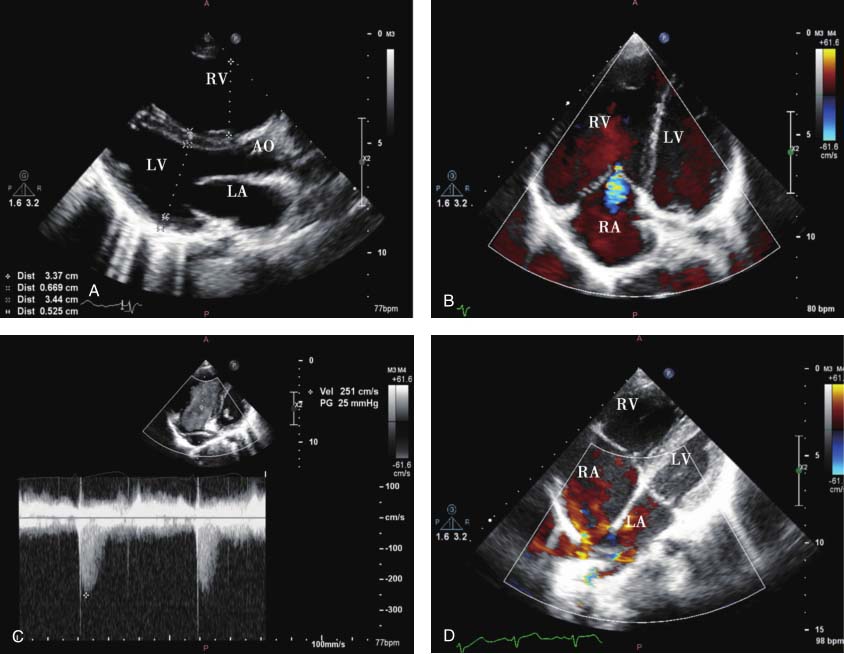

图22-1 患儿超声心动图表现

A.左心室长轴切面显示右心房及右心室增大;B.四腔心切面显示右心房及右心室增大,三尖瓣少量反流;C.三尖瓣反流频谱估测肺动脉压力;D.非标准四腔心切面彩色多普勒显示右中肺静脉回流入右心房;E.二维超声非标准四腔心切面显示房顶部房间隔缺损;F.剑突下双心房切面彩色多普勒显示心房水平左向右分流。

本病例左心室长轴切面显示右心房及右心室明显增大,提示存在左向右分流可能。非标准四腔心切面可进一步明确房间隔缺损及肺静脉异位引流至右心房。部分型肺静脉异位引流合并房间隔缺损时,分流量较单纯房间隔缺损或部分型肺静脉异位引流大。此类部分型肺静脉异位引流可于斜四腔心切面直接观察到肺静脉回流途径,相对不易漏诊和误诊。